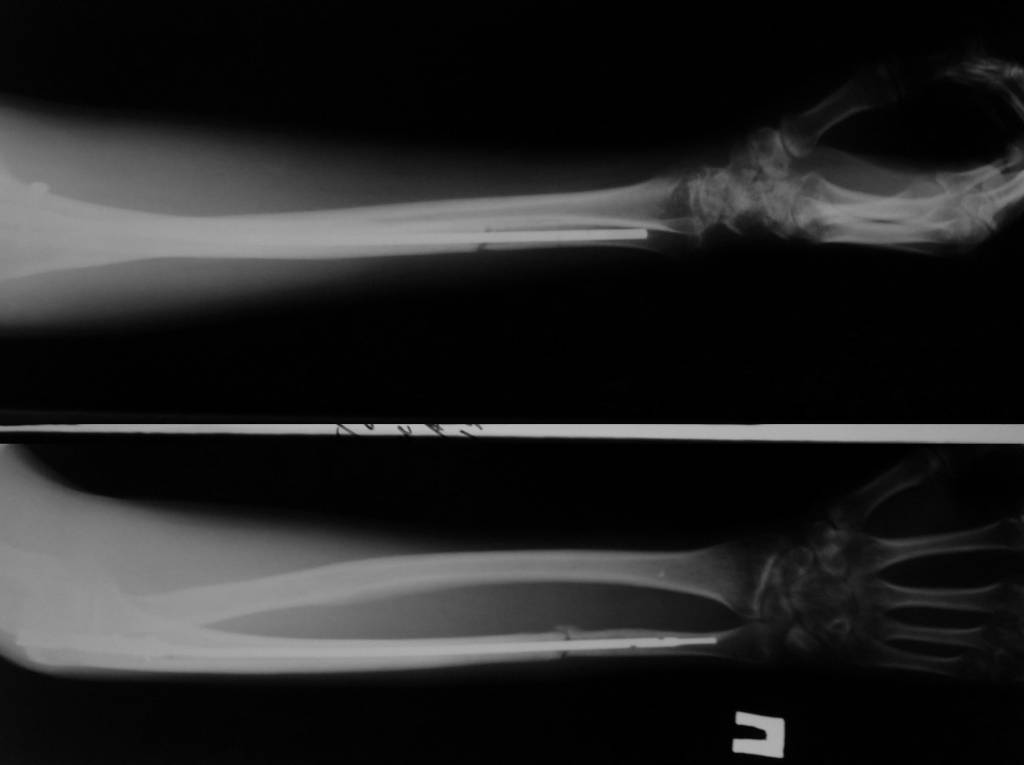

6 февраля 2011 года сломал локтевую кость со смещением. Поставили аппарат Илизарова. Вместо двух месяцев проносил четыре, срасталось медленно. Сняли, сказали разрабатывать и через 5 дней кость сместилась опять. 15 июня сделали вторую операцию, поставили дорогой стержень в кость, закрепили в области локтя на два шурупа. Перелом у меня в 1/3 ближе к кисти. Вторую часть кости одели на стержень, но не закрепляли. Также освежили концы костей, так как они зарубцевались и костномозговые каналы полностью закрылись.Месяц проносил лангету до плеча, потом сказали разрабатывать руку, но постепенно я начал чувствовать шевеление в месте перелома и щас чувствую.Щас опять хотят загипсовать уже всю руку на 2 месяца, но мне кажется что концы костей опять зарубцевались за 2 месяца зарастания "впустую" и даже в гипсе уже не срастется.По снимкам щель отчетливо видна. На руке вместе перелома нащупывается шишечка. Предположительно, что 1/3 кости, которая не прикручена к стержню, имеет хождение вдоль стержня.Кисти еще после аппарата Илизарова не поворачивается ладонью вверх и вниз. Имеет ход градусов 15 влево вправо и все.Что мне делать? Как еще восстановить руку? Еще одна операция? Исправит ли гипс на 2 месяца проблему? Мне 28 лет.

По этому снимку ничего плохого не видно. Нужна и вторая проекция. Когда сделан снимок?

Для того, чтобы предложить конкретный план выхода из этой ситуации, нужно более точное представление о проблеме - надо хотя бы увидеть свежие рентгенограммы всего предплечья в двух проекциях.